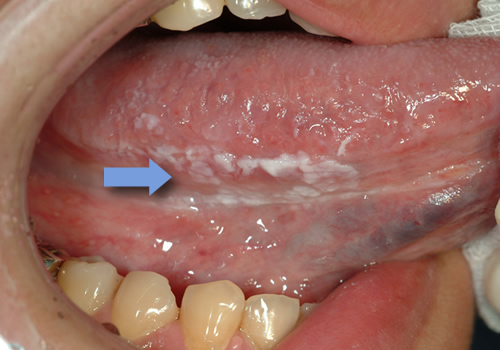

白板症

白板症は、罹患率が平均3%前後と言われており、40歳台以降に多く、喫煙者が非喫煙者の6倍という報告もあります。舌や歯肉、頬粘膜、口蓋など様々な部分に出来ます。

歯で噛んでしまうことやあわない入れ歯による慢性の刺激でも角化による白色病変を呈する場合がありますが、原因がはっきりしていれば、まずはそれを除去することが先決です。白板症は前がん病変の一つです。